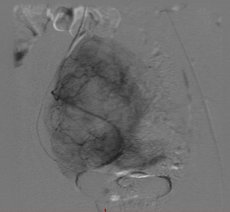

Bei der Embolisation wird über die Leiste ein sehr dünner Schlauch (Katheter) in die Arterie eingeführt und unter Röntgenkontrolle von einem spezialisierten Radiologen bis zur Gebärmutterarterie vorgebracht. Dort werden feinste Kügelchen (Microsphären) in die Myome gespritzt, so dass diese absterben und die Beschwerden verschwinden. Die Gebärmutter selbst bleibt erhalten.